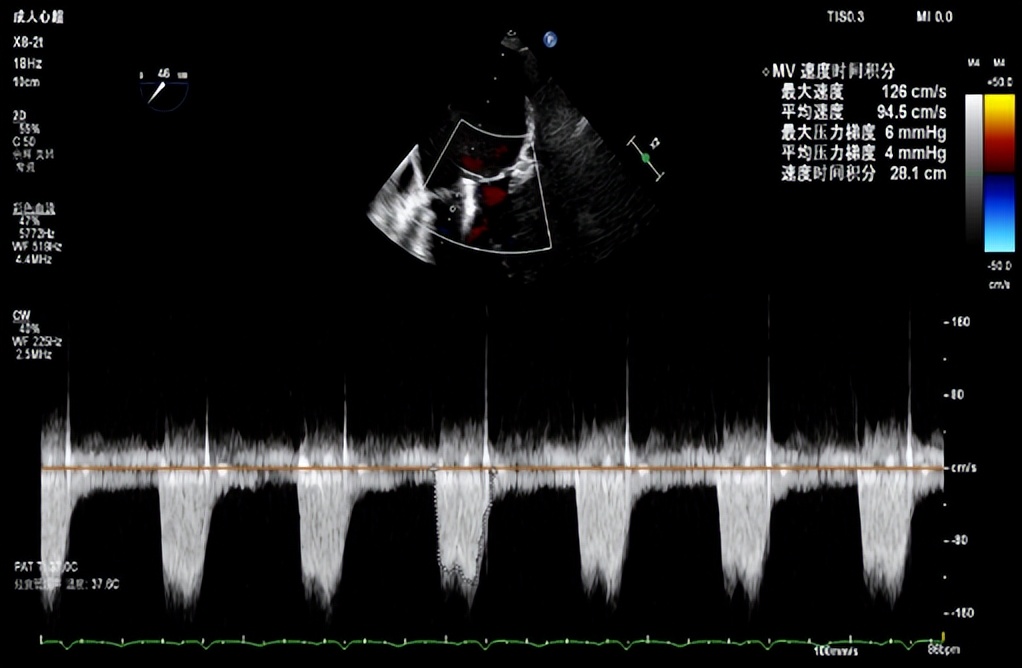

患者男性,71岁,反复心衰发作,心脏彩超示重度二尖瓣返流(MR 4+)(图二、三),既往糖尿病病史10余年、单侧颈内动脉闭塞7年余,2年前行冠脉搭桥及主动脉动脉瘤支架植入术,本次心衰急性发作合并严重肺部感染,经口气管插管呼吸机辅助并对症药物治疗,效果欠佳;存在较高心功能进一步恶化、呼吸循环衰竭、恶性心律失常、猝死等风险。

图二(食道超声心动图二尖瓣大量返流)

图八(评估夹合后二尖瓣无狭窄)